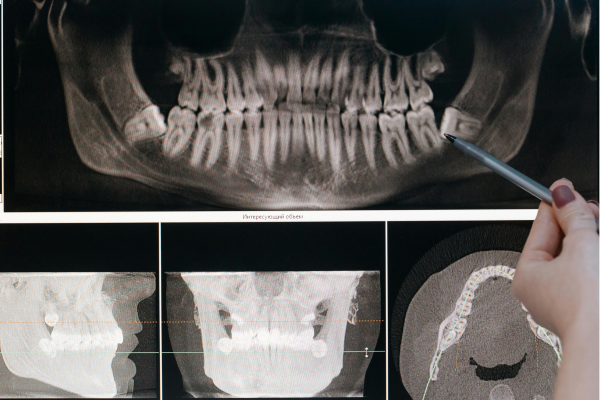

当院では、矯正前に必ずCTスキャンやレントゲン撮影を行い、骨の厚みや密度、歯の角度を正確にチェックしています。

矯正治療の可否をより正確に判断するために、 セファロ撮影や口腔内スキャンに加えて、3次元CT撮影装置も導入。2次元・3次元の両面から分析を行うことで、 矯正治療が「できる・できない」をより多角的に診断いたします。

セファロ撮影や口腔内のスキャンはもちろん、3次元CT撮影装置も設置しており、2次元・3次元での検査・分析を多角的に行うことができるので、矯正治療が「できる・できない」をしっかりと判断します。